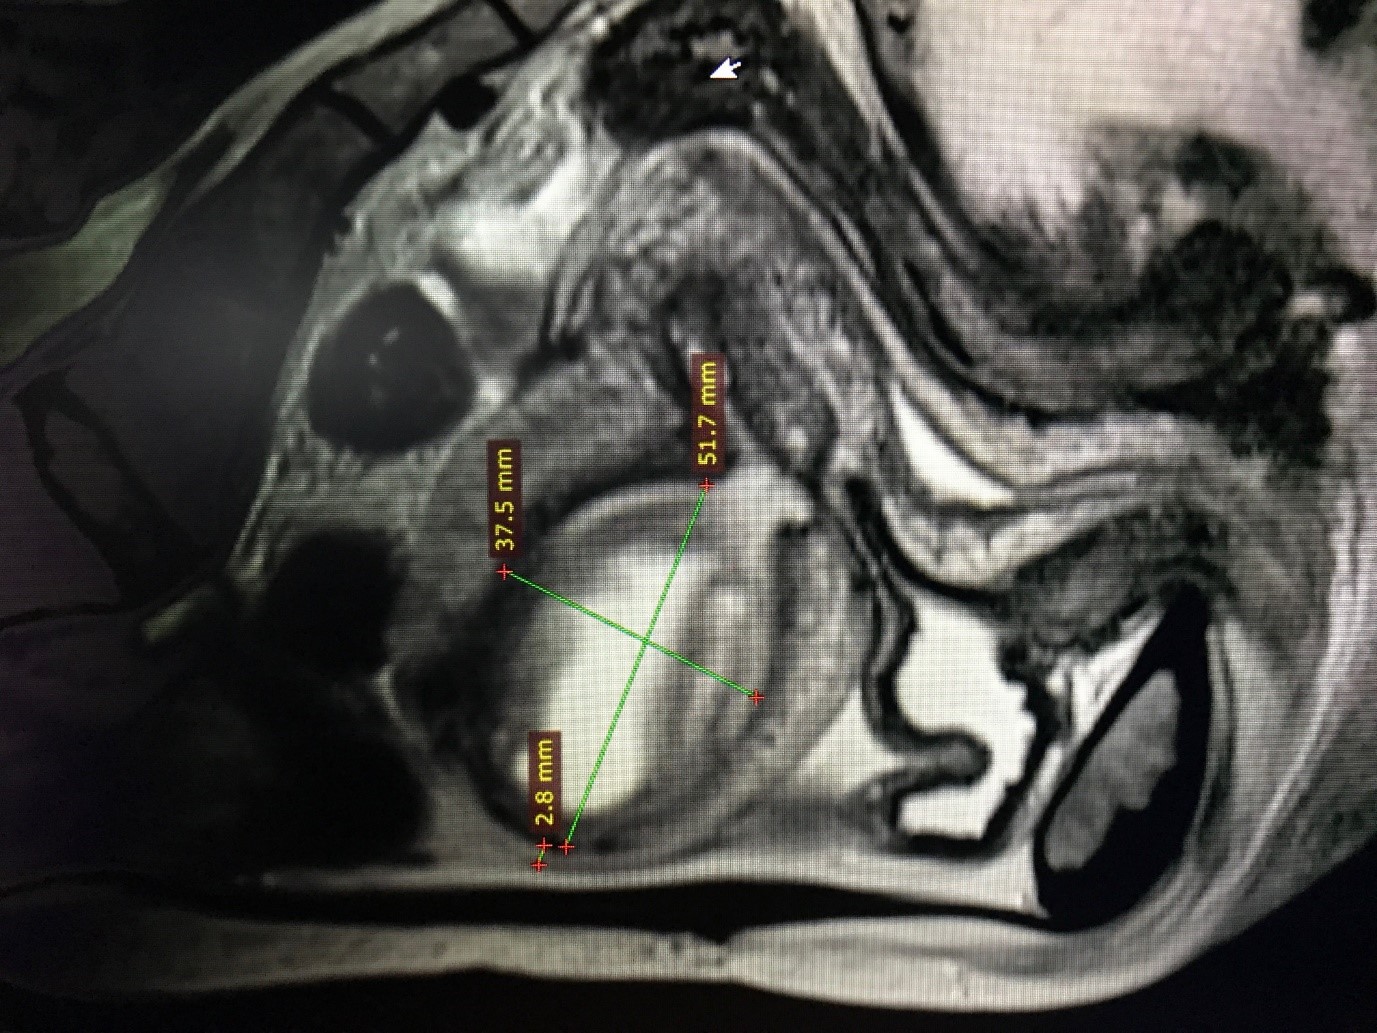

“Datorita imaginii bine delimitate ecografic am luat decizia de a efectua un examen RMN cu substanta de contrast si aici am exploatat experienta colegei mele medic imagist doamna dr. Emilia Diaconu. Rezultatul pe care l-am obtinut nu ar fi fost posibil fara profesionalismul dumneaei. Ceea ce am aflat in urma realizarii investigatiei a contat foarte mult: diametrul mare al tumorii, era vorba de un diametru de 55 mm in axul lung al uterului, dar cu delimitare clara fata de structurile din jur. S-a ridicat suspiciunea de fibrom uterin necrobiozat si in acel moment m-am gandit la un diagnostic diferential cu un adenomiom. Acest lucru m-a determinat sa iau decizia de a realiza o rezectie histeroscopica a respectivei formatiuni tumorale” caracterizeaza dr. Narcis Stoica situatia parcursa pentru stabilirea formei optime de interventie.